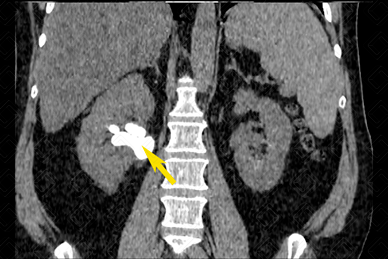

Texto alternativo para a imagem Figuras 1 e 2. Créditos: Dra. Elazir Mota - Rio de Janeiro/RJ

Descrição das figuras 1 e 2: Tomografia computadorizada de abdome, plano coronal, evidenciando cálculos renais bilaterais (setas vermelhas). Observe, ainda, a presença de cálculo coraliforme à direita, “moldando” a pelve renal (seta amarela).

• Tomografia computadorizada do abdome e pelve: E xame de escolha para avaliação de cálculos renais. Neste exame, todos os cálculos são bem visualizados já que apresentam densidade superior a 200 UH e há bom contraste com as partes moles adjacentes (a única exceção são os cálculos de Indinavir). Nestes casos, a tomografia deve ser realizada sem a administração do contraste venoso. Os cálculos apresentam-se neste exame como estruturas espontaneamente densas (f iguras acima).